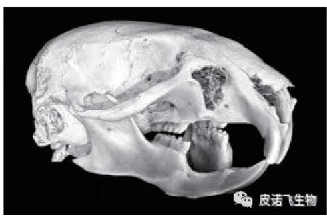

关节组织 生殖器组织

头部组织